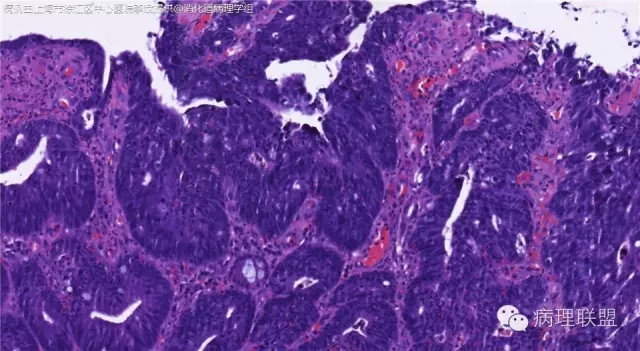

男,72岁,距肛门口30cm息肉。大体:灰白结节1.5*1*0.8cm拟发管状腺瘤并部分区高级别,请各位老师指导!(病例由上海市徐汇区中心医院 李斌 提供,致谢!)

这一例有两种不同看法,按WHO标准,为高级别,按实际工作,要发粘膜内癌。WHO第三版与第四版均提出,侵犯至粘膜下层才能诊断为癌,声称结直肠粘膜内没有淋巴管,发生转移的概率较小,但是粘膜内有血管,肿瘤侵出粘膜腺体基膜以外,就能侵犯血管,照样可以发生血道转移。文献报告与我们的工作实践,发现腺瘤、高级别(没有侵出基膜)的患者,同样有发生血道转移。因此,我们废弃了这一条WHO标准(不是所有的WHO标准都是一定要执行的)。只要异型增生腺体呈毛刺状、迷芽状侵出粘膜腺体基膜,位于粘膜肌层以内,就发粘膜内癌。

@李斌 结肠腺瘤这例我认为已经有黏膜下浸润了,因为有些腺体间的间质已经不是固有膜间质而是促结缔组织增生反应的间质了。但即使有浸润癌,如果息肉完整摘除、癌成分分化好、没有脉管瘤栓、浸润癌距切缘大于1mm(日本标准还要看浸润癌超出黏膜肌深度和肿瘤出芽情况),也不需要进一步治疗。所以,对于这类可能存在争议的病变,特别是息肉已经完整切除的病例,诊断的关注点就应该放在寻找需不需要进一步治疗的证据上了。@邓永键 2010版WHO在腺瘤部分的陈述中已经写出对于有局灶浸润性生长的病例也可以称黏膜内癌,他们在悄悄的让步。